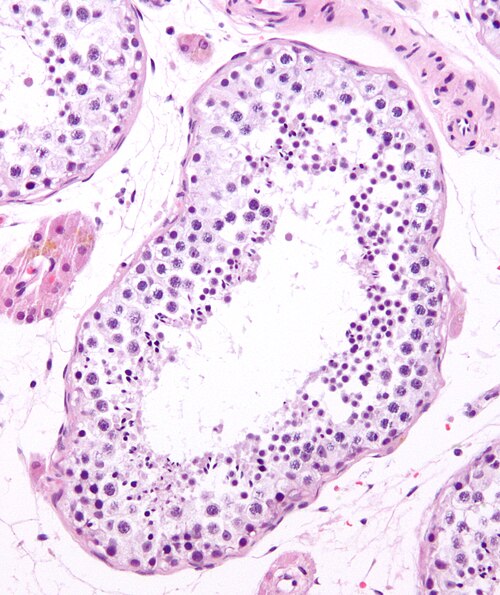

The production of sperm is a complex process and requires normal functioning of the testicles (testes) as well as the hypothalamus and pituitary glands — organs in your brain that produce hormones that trigger sperm production.

Once sperm are produced in the testicles, delicate tubes transport them until they mix with semen and are ejaculated out of the penis. Problems with any of these systems can affect sperm production.

Also, there can be problems of abnormal sperm shape (morphology), movement (motility) or function.

However, often the cause of low sperm count isn’t identified.